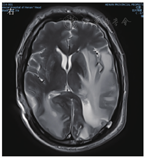

患者男,63岁,因"间断发热1年"于2020年6月29日入河南大学人民医院。患者1年前无明显诱因下出现发热,体温最高达38.0 ℃,伴有反应迟钝、吞咽困难、饮水呛咳、颈部硬肿,无咳嗽、咳痰,无胸闷、呼吸困难。患者于外院查血常规示感染相关指标高,CT检查示颅内感染可能(具体不详),予"美罗培南、万古霉素"抗感染治疗,体温可降至正常,但很快反复;后多次因"颅内感染"住院,予抗感染治疗,疗效差。4月余前因颅内高压、脑积水于外院行脑室-腹腔分流术。3月21日外院头颅MRI检查示左侧枕部颅板下积液、左侧颞枕顶叶明显水肿,增强后明显强化;颅脑术后改变。5月21日肺部CT检查示双肺多发结节影、条索影,考虑慢性炎症。为求进一步诊治来河南大学人民医院,门诊以"发热待查:颅内感染?脑室-腹腔分流术后"收入感染科。患者自发病来,神志欠清,精神差,食欲及睡眠可,二便正常,体质量较前无明显减轻。既往史:2003年因颈椎破坏行植骨术;2013年因"发热伴头痛"发现颅内病变,曾就诊于多家医院均未明确诊断,病情缓慢进展;2018年因"头痛加重"行颅内病变切除术,术后考虑感染性病变,间断抗感染治疗,病情仍无改善。体格检查:体温为36.8 ℃,脉搏为88次/min,呼吸为20次/min,血压为135/85 mmHg(1 mmHg=0.133 kPa)。神志欠清,反应迟钝,对答欠切题,计算力下降。双侧额纹变浅,闭目力差,双侧鼓腮力、咀嚼力差;伸舌困难,舌不能完全伸出;双侧瞳孔等大等圆,眼球活动度差,尤其上视、右视时明显,对光反射迟钝,视力下降;颈部红肿、僵硬,无压痛;双肺听诊呼吸音清,未闻及干、湿啰音;心前区无隆起,心界不大,律齐,各瓣膜听诊区未闻及心脏杂音及心包摩擦音;腹部平软,无压痛,肝脾肋下未及,移动性浊音阴性,肠鸣音正常;双下肢无水肿,肌力3级,腱反射(-),病理征(+)。考虑为免疫性疾病,予补液、营养支持等对症治疗。实验室检查:IgG为37 910 mg/L,抗髓过氧化物酶抗体为24.21 RU/mL,IgE为208.3 IU/mL,IgG4为10 400 mg/L;IL-6为115.88 ng/L;ESR为106 mm/1 h;CRP为146.36 mg/L;降钙素原为0.12 μg/L;血常规、尿常规、粪便常规、游离三碘甲腺原氨酸、游离甲状腺素、促甲状腺激素、T.SPOT.TB检测、β-D-葡聚糖试验、半乳甘露聚糖抗原试验、EB病毒DNA、CMV DNA、布鲁菌抗体、肿瘤标志物均阴性。6月30日胸部CT检查示双肺多发结节,见图1。7月2日头颅MRI平扫+增强检查示脑内多发异常信号影;后纵裂池处脑膜、小脑幕及左侧颞部硬脑膜增厚并明显强化;左侧枕叶局部脑穿通畸形形成,见图2。进一步行腰椎穿刺脑脊液检查示单核细胞计数为66×106/L,蛋白质为6.02 g/L,葡萄糖为2.02 mmol/L,氯化物为119.9 mmol/L。考虑为IgG4相关疾病(immunoglobulin-G4 related disease,IgG4-RD)。7月2日请病理科会诊外院术中脑组织病理切片,结果示(左枕)纤维组织增生伴玻璃样变性,局部胶原化,淋巴袖套结构可见,血管周围及硬化间质内见较多淋巴细胞及浆细胞浸润,浆细胞形态成熟,见图3;免疫组织化学染色示纤维及血管周边可见多量IgG4+浆细胞浸润,IgG4+浆细胞约为50~100个/高倍视野,见图4。根据患者检查结果和多科室专家会诊,诊断为IgG4-RD,累及中枢、肺部、皮肤、骨骼。由于患者病变侵犯脑干,有脑水肿、颅内压升高等表现,可能出现呼吸、心跳骤停等严重并发症,与患者家属沟通患者病情。7月10日开始予甲泼尼龙(500 mg,1次/d,静脉滴注)冲击联合丙种球蛋白(20 g,1次/d,静脉滴注)治疗。当天患者眼球转动基本正常,进食无呛咳,意识、反应和言语明显好转,颈部硬肿好转。予静脉滴注甲泼尼龙500 mg 3 d、240 mg 3 d、120 mg 3 d、80 mg 3 d、40 mg 3 d,以及静脉滴注丙种球蛋白20 g (1次/d) 5 d,患者症状明显改善,复查IgG、IgG4、ESR、CRP均较前下降。7月13日肺部CT检查示双肺结节明显缩小,见图5。7月19日头颅MRI检查示颅内局部脑水肿减轻,后纵裂池处脑膜、小脑幕及左侧颞部硬脑膜病变缩小,见图6。患者症状逐渐好转,7月24日患者及家属要求出院。出院后继续予甲泼尼龙治疗,后联合吗替麦考酚酯,患者一般情况稳定,定向力、记忆力、认知力正常,言语流利。